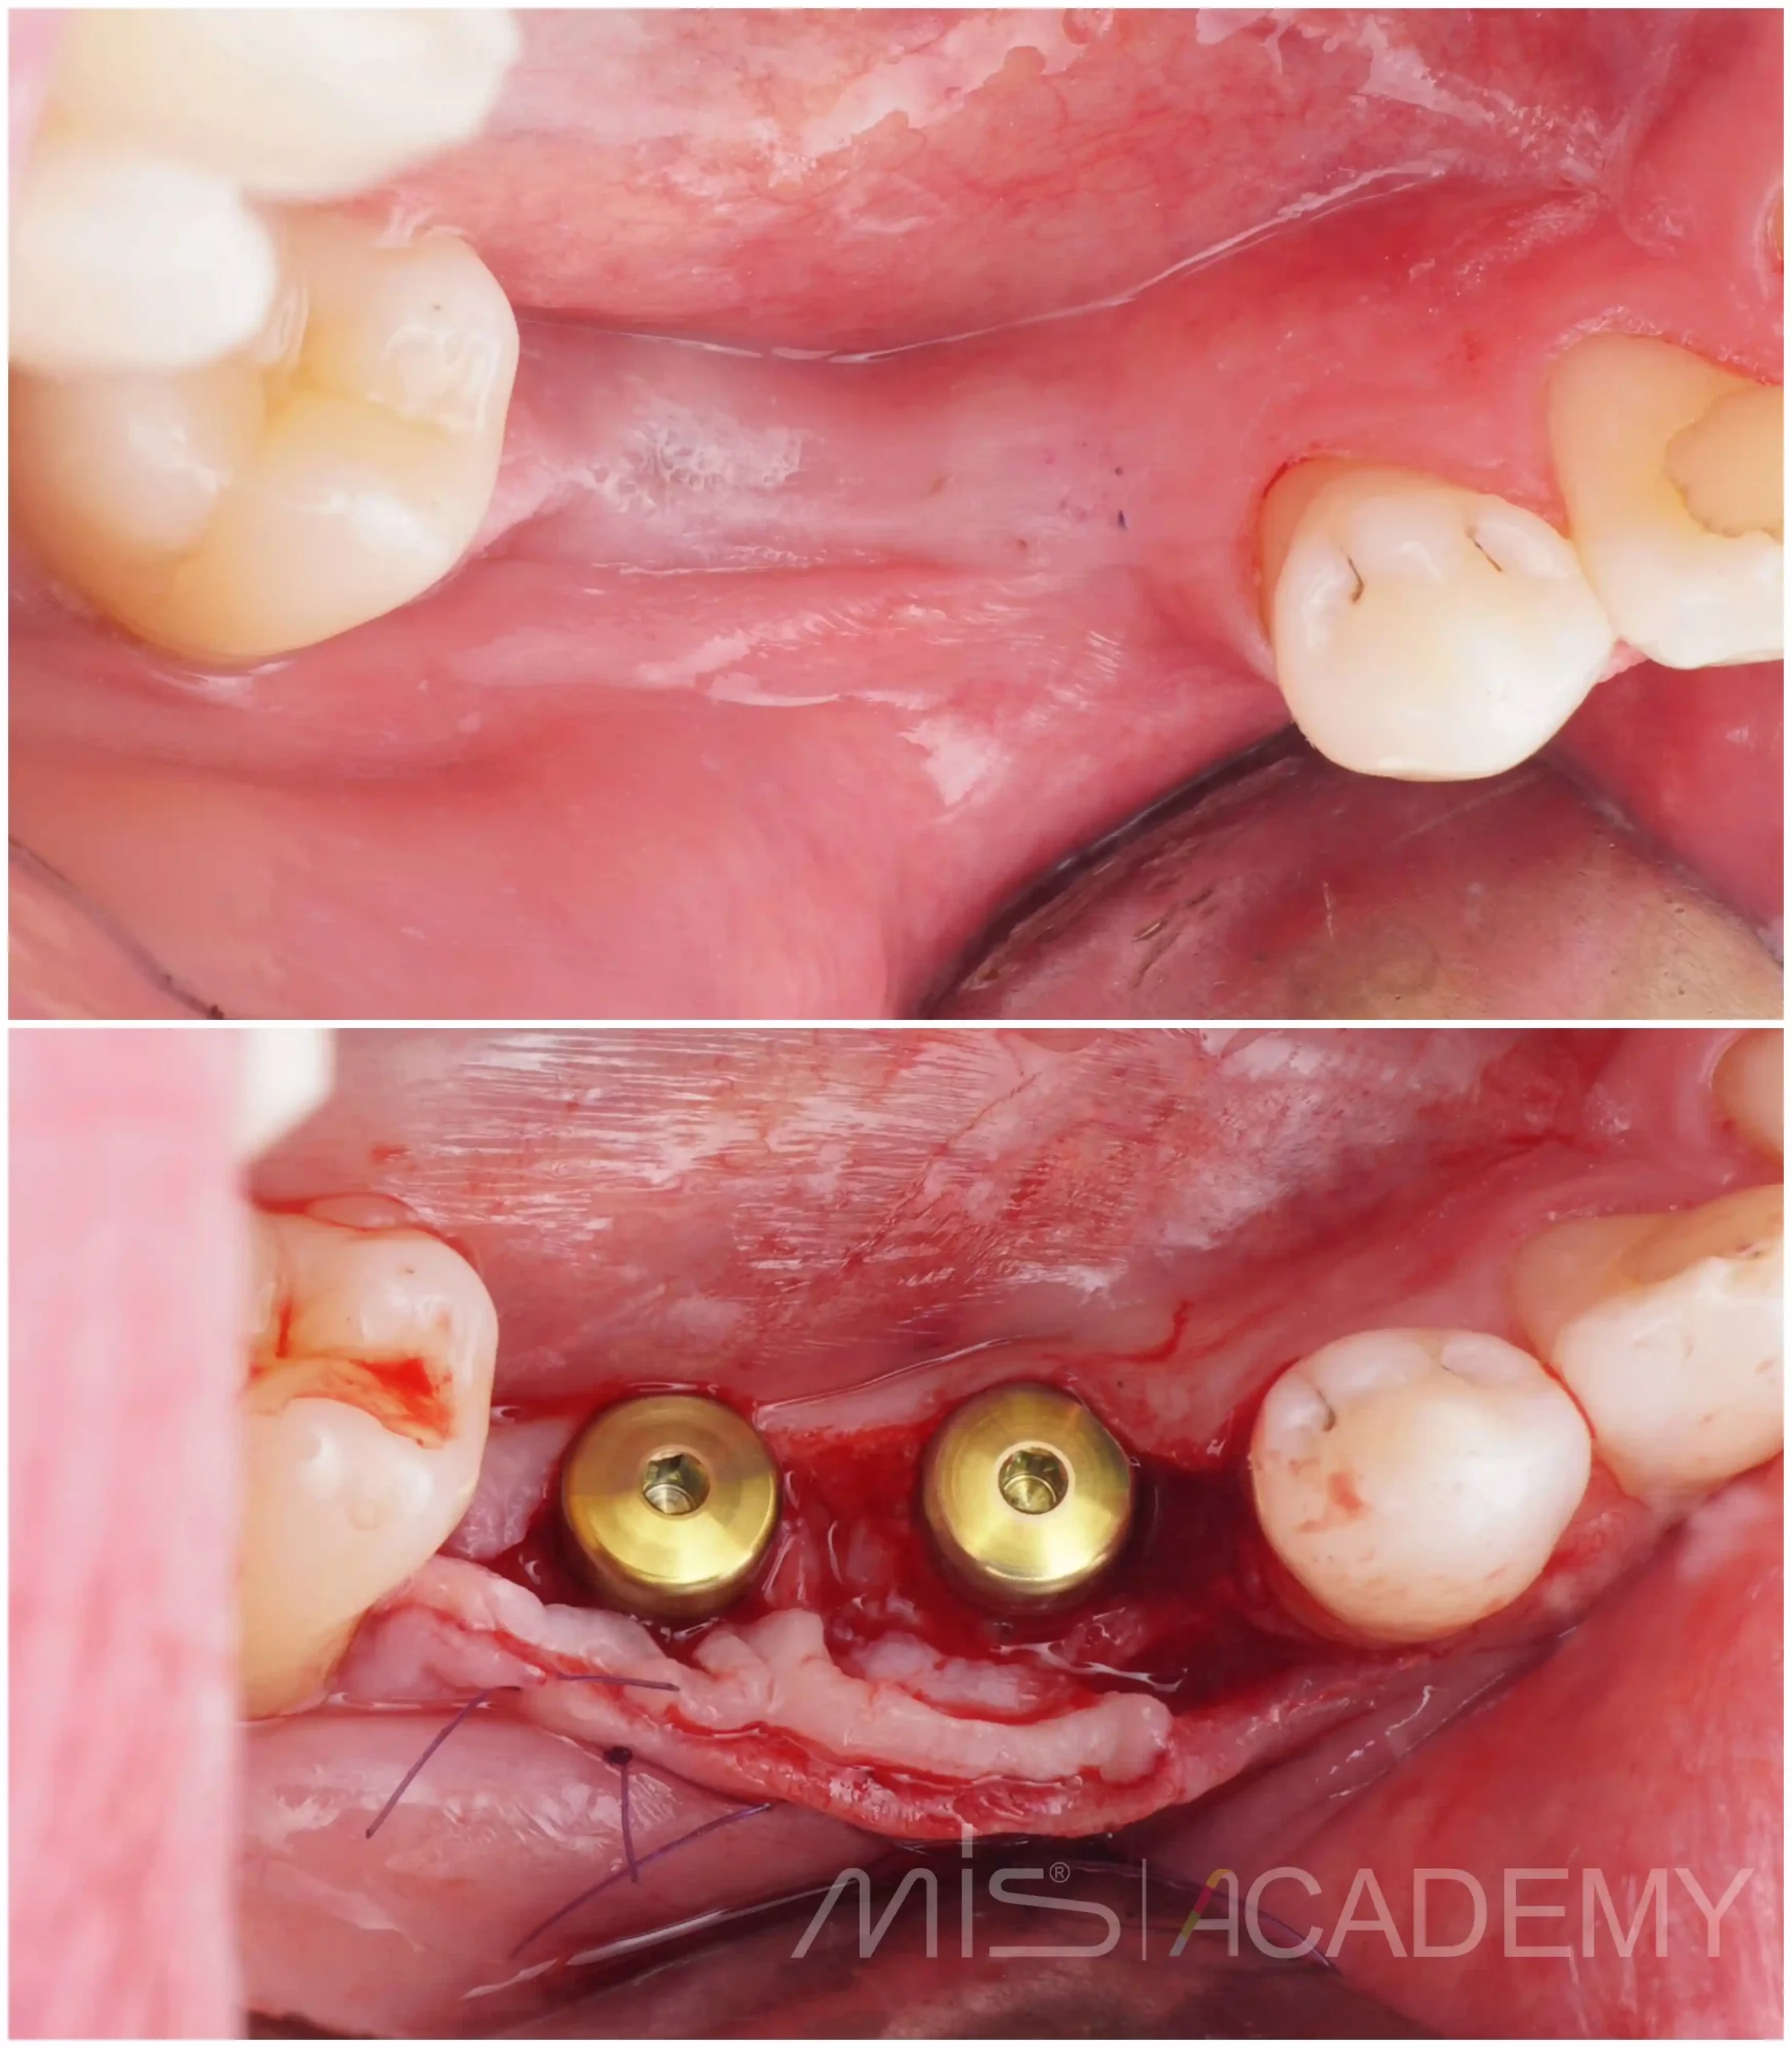

— По хирургическому шаблону установили имплантаты MIS Seven высотой 8 и 6 мм.

— Сразу использовали формирователи десны 3 мм.

— Мягкие ткани дополнительно доработали: выполнена пластика ССТ на фдм методом пончо и вестибулярно.

— Рана ушиты наглухо поверх формирователей.